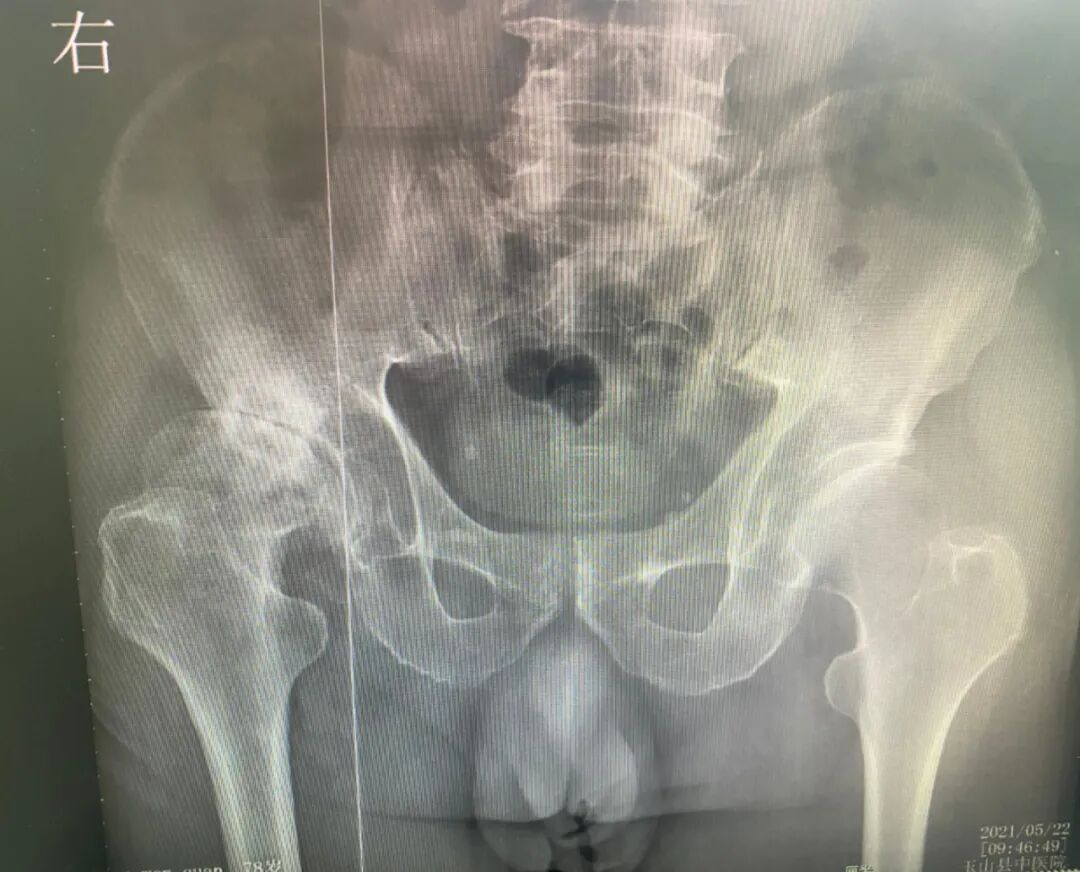

家住玉山必姆的俞大爷,右髋部疼痛不适8年余。早在8年前,俞大爷就被诊断为右股骨头缺血性坏死,前往上海、浙江等大型医院就诊时,无一例外得到的是一笔不菲的手术耗材告知,俞大爷只能心生退意。8年来,大爷右髋部的疼痛如影随形,渐渐的,“根治右髋部的疼痛”似乎是埋藏在他心底的一一个难以实现的愿望。

术前